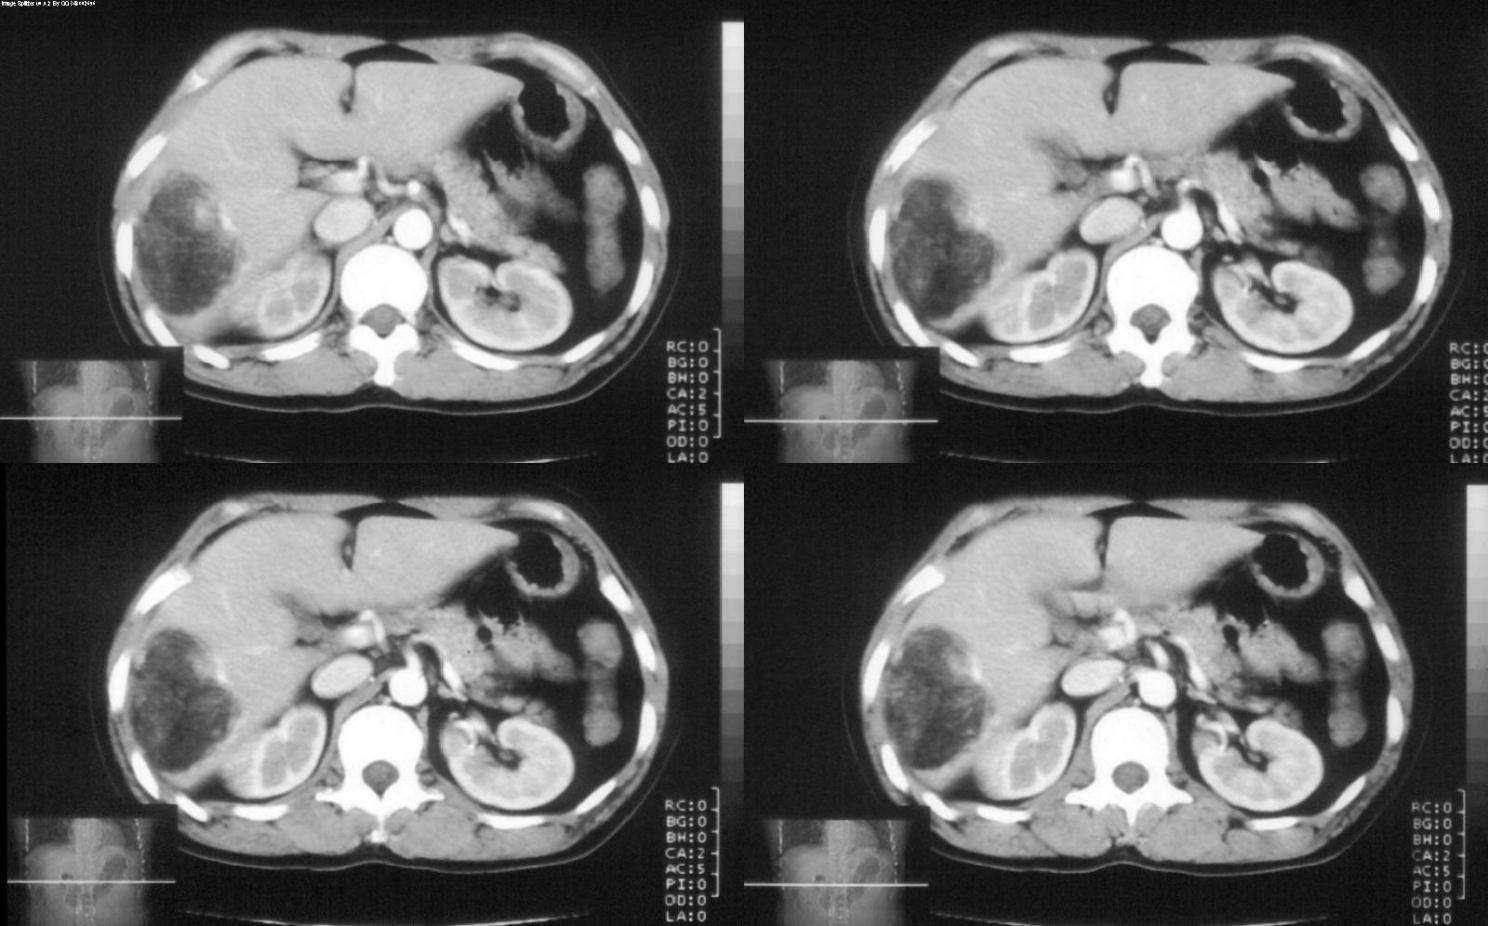

标题: CT28180:女性,42岁。体检时发占位。 [打印本页]

标题: CT28180:女性,42岁。体检时发占位。

肝脏血管平滑肌脂肪瘤,边界结节样血管影持续性强化。

支持 肝右叶血管平滑肌脂肪瘤。

病灶多种成分,以脂肪为主,可见强化的血管肌肉成分,边界较清晰,综合考虑血管平滑肌脂肪瘤可能性大